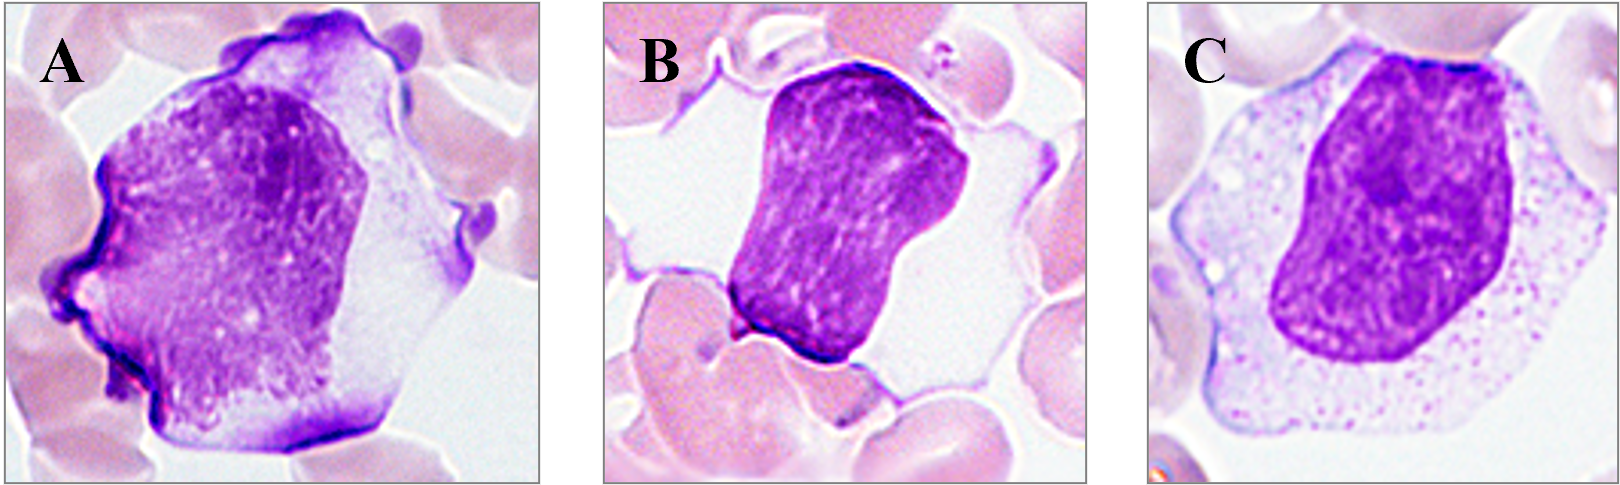

| 【助言1】 | ご質問から細胞質の青味が強めとは異型リンパ球(反応性リンパ球)、青味が少ないとは大リンパ球を考えます。単球も含めて鑑別ポイントを解説致します。下図に異型リンパ球(A)、大リンパ球(B)、単球(C)を提示します。大きさは異型リンパ球と単球が16μmを超えることが多く、異型リンパ球は核クロマチンの粗剛さと細胞質の好塩基性(青色)が強く、大リンパ球はクロマチンの粗剛さは同じですが、細胞質の好塩基性は薄れ(淡青色)、単球はクロマチンは繊細さで細胞質の好塩基性は薄れ(灰青色)微細顆粒が充満して空胞をもつことが特徴になります。 | |